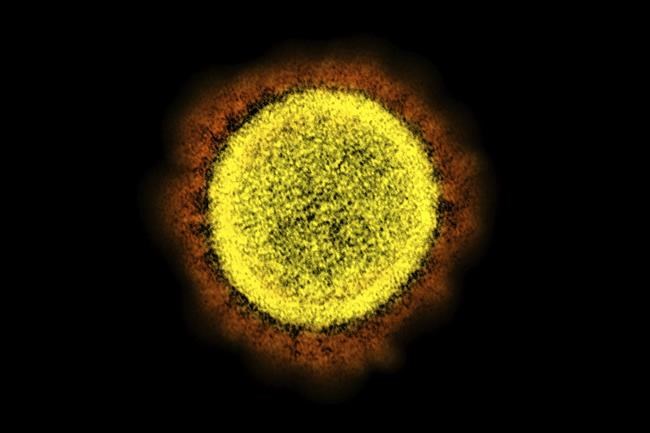

The coronavirus mutant widely known as “stealth omicron” is now causing more than a third of new omicron cases around the world, but scientists still don’t know how it could affect the future of the pandemic.

Researchers are slowly revealing clues about the strain, a descendant of omicron known as BA.2, while warily watching it become ever more prevalent.

BA.2 has lots of mutations. It’s been dubbed “stealth” because it lacks a genetic quirk of the original omicron that allowed health officials to rapidly differentiate it from delta using a certain PCR test. So while the test can detect a BA.2 infection, it looks like a delta infection.